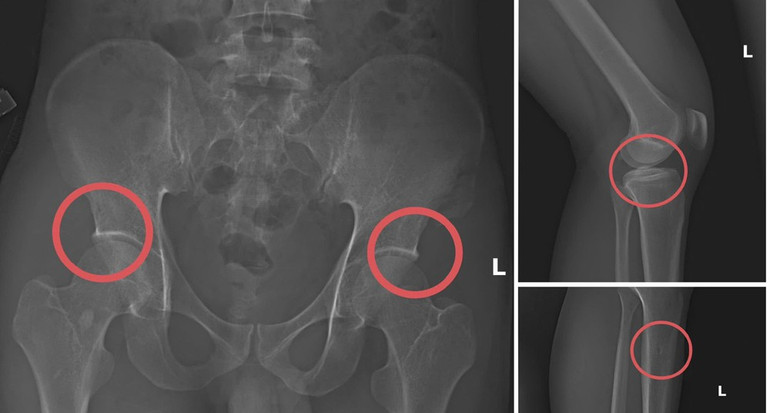

Theo điều tra ban đầu, Tạ Minh Châu (SN 1995), nguyên cán bộ Trung tâm Y tế huyện Cẩm Khê (cũ), được xác định là kẻ chủ mưu, trực tiếp xây dựng cả một “quy trình trục lợi” tinh vi. Lợi dụng kiến thức chuyên môn về xương khớp và sự am hiểu cơ chế chi trả bảo hiểm, Châu tổ chức lôi kéo người dân mua bảo hiểm, sau đó tiêm thuốc mê rồi dùng kim tiêm, búa… để đục vỡ xương – khớp, tạo ra thương tích giống hệt tai nạn thật.

Không dừng lại ở việc gây thương tích, Châu còn chỉ đạo các đối tượng dựng hiện trường giả như điện giật ngã, trượt chân suối… để hợp thức hóa bệnh án, đánh lừa quy trình giám định. Nhờ các “mẹo nghiệp vụ” này, nhiều hồ sơ được chi trả với giá trị lớn, khiến các công ty bảo hiểm bị rút tiền trong thời gian dài mà không phát hiện.